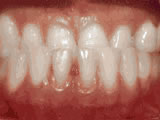

Non-braces treatment

non braces treatment beforeBefore

non braces treatment afterAfter

Sometimes braces are not needed to get noticeable improvements in tooth alignment. This patient was first seen at age seven for crowding of the lower permanent teeth. A procedure was performed to reduce the width of the adjacent baby teeth and the permanent incisors aligned on their own in nine months.